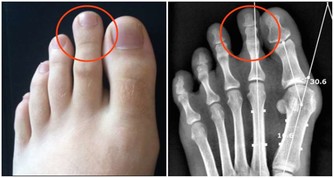

最後送大家一個中醫護肝穴位小技巧——常按肝經的易堵塞穴位

每天疏通1-2次,每次3-5分鐘,直到穴位不痛。隔段時間再探查疏通一番。